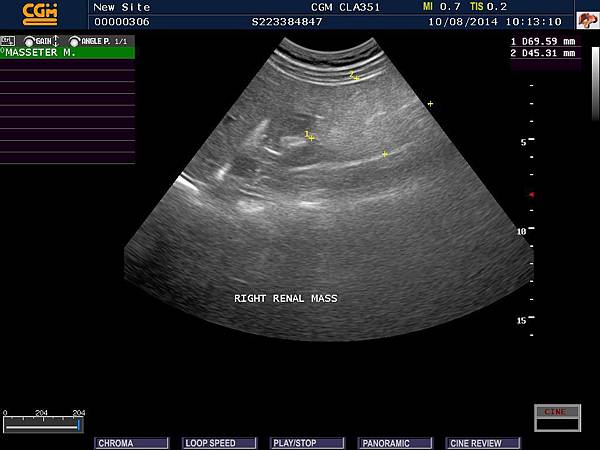

前陣子接到一份回診單,看完之後著實鬆了一口氣,另外,也想紀錄這一件事情做為將來衛教資料,患者是一位年輕女性,剛好有一天中午來到門診,主述下腹部疼痛,因為患者有便秘病史,問診與理學檢查後,考慮或許是便秘所造成,想說開一些軟便藥物就可以了,不知那一天,如何心血來潮 ( 或許是醫師的直覺吧 ),想說超音波看一下是否有什麼異常,結果 ...,竟然發現兩側腎臟腫瘤,如圖:

腎臟腫瘤 B

當下甚怕自己中午還沒吃,血糖有些低,是否有所誤判,便囑咐患者過幾天回診,再確定一下,數天後,患者表示狀況改善,超音波顯示兩側數個4至7公分的腫瘤,當下想說很有可能是惡性腫瘤,趕快開立轉診單,後續追蹤吧 ! 但心中總有些許惆悵,想說這麼年輕小姐將來如何呢 ? 腫瘤是否能摘除乾淨嗎 ? 是否需要長期洗腎丫 ? 今晚終於接到回診單啦 ! 護士小姐、藥師與我都懷者忐忑的心情揭曉答案,整體報告顯示腎功能正常與懷疑兩側良性血管肌肉脂肪腫瘤,接著馬上把消息告訴患者,分享喜悅的心情。